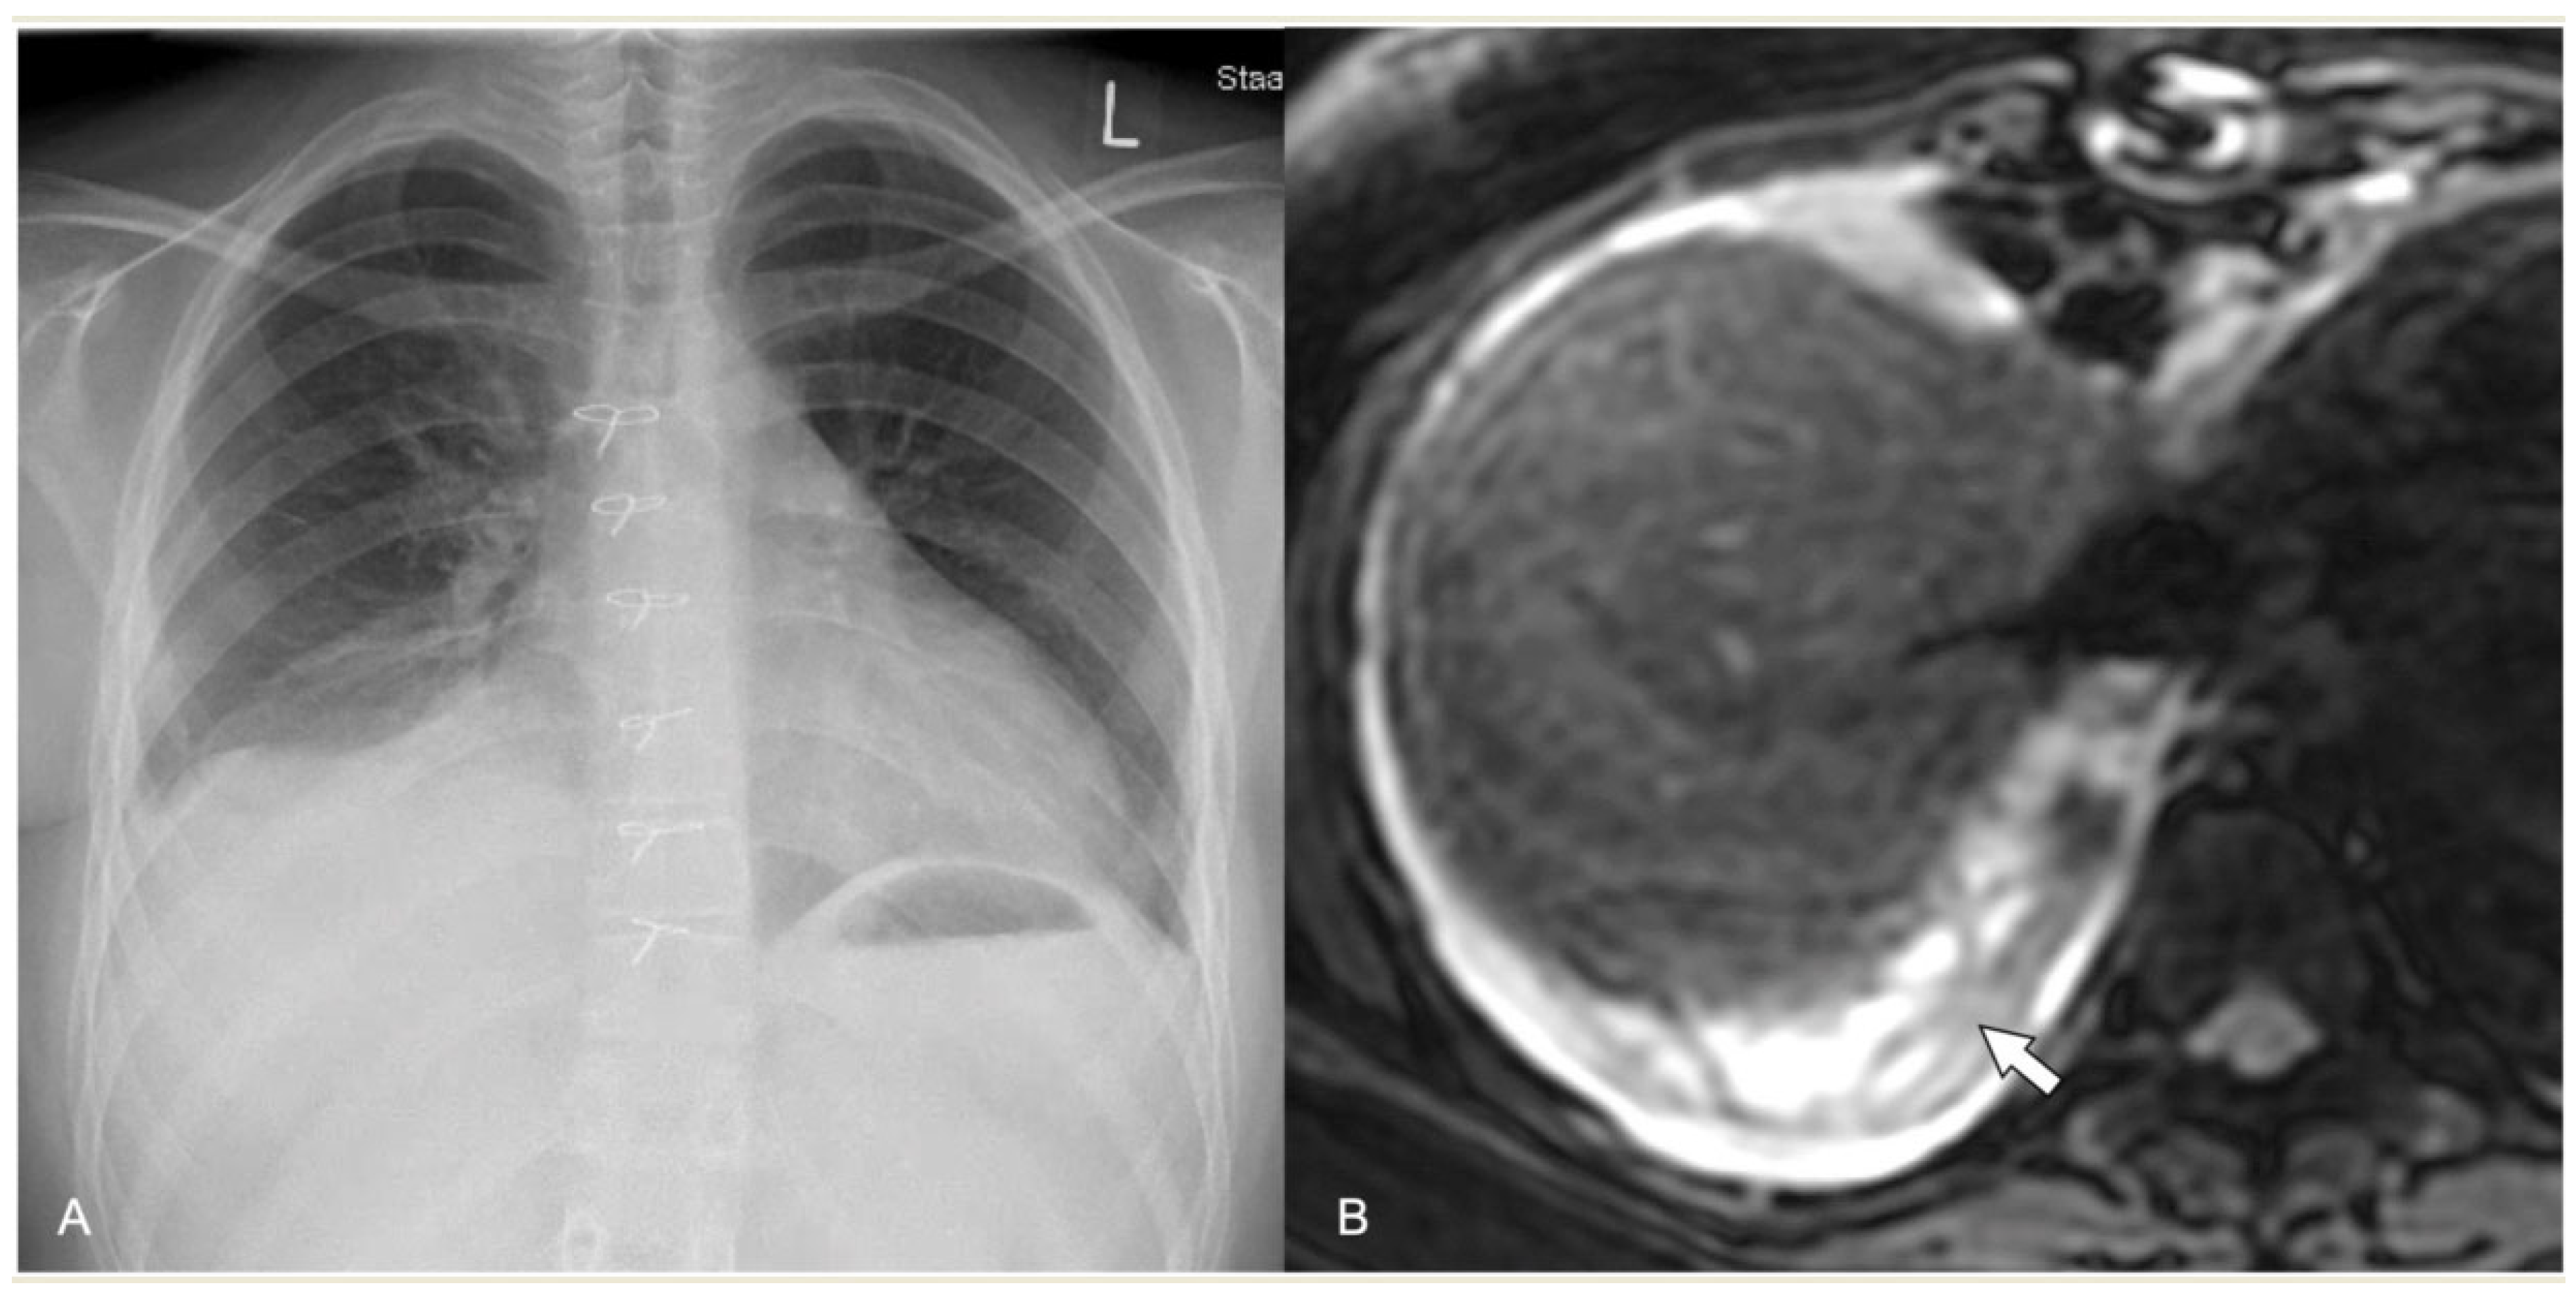

2.4.1. Pleural Effusion—Empyema

2.4.4. Abscess